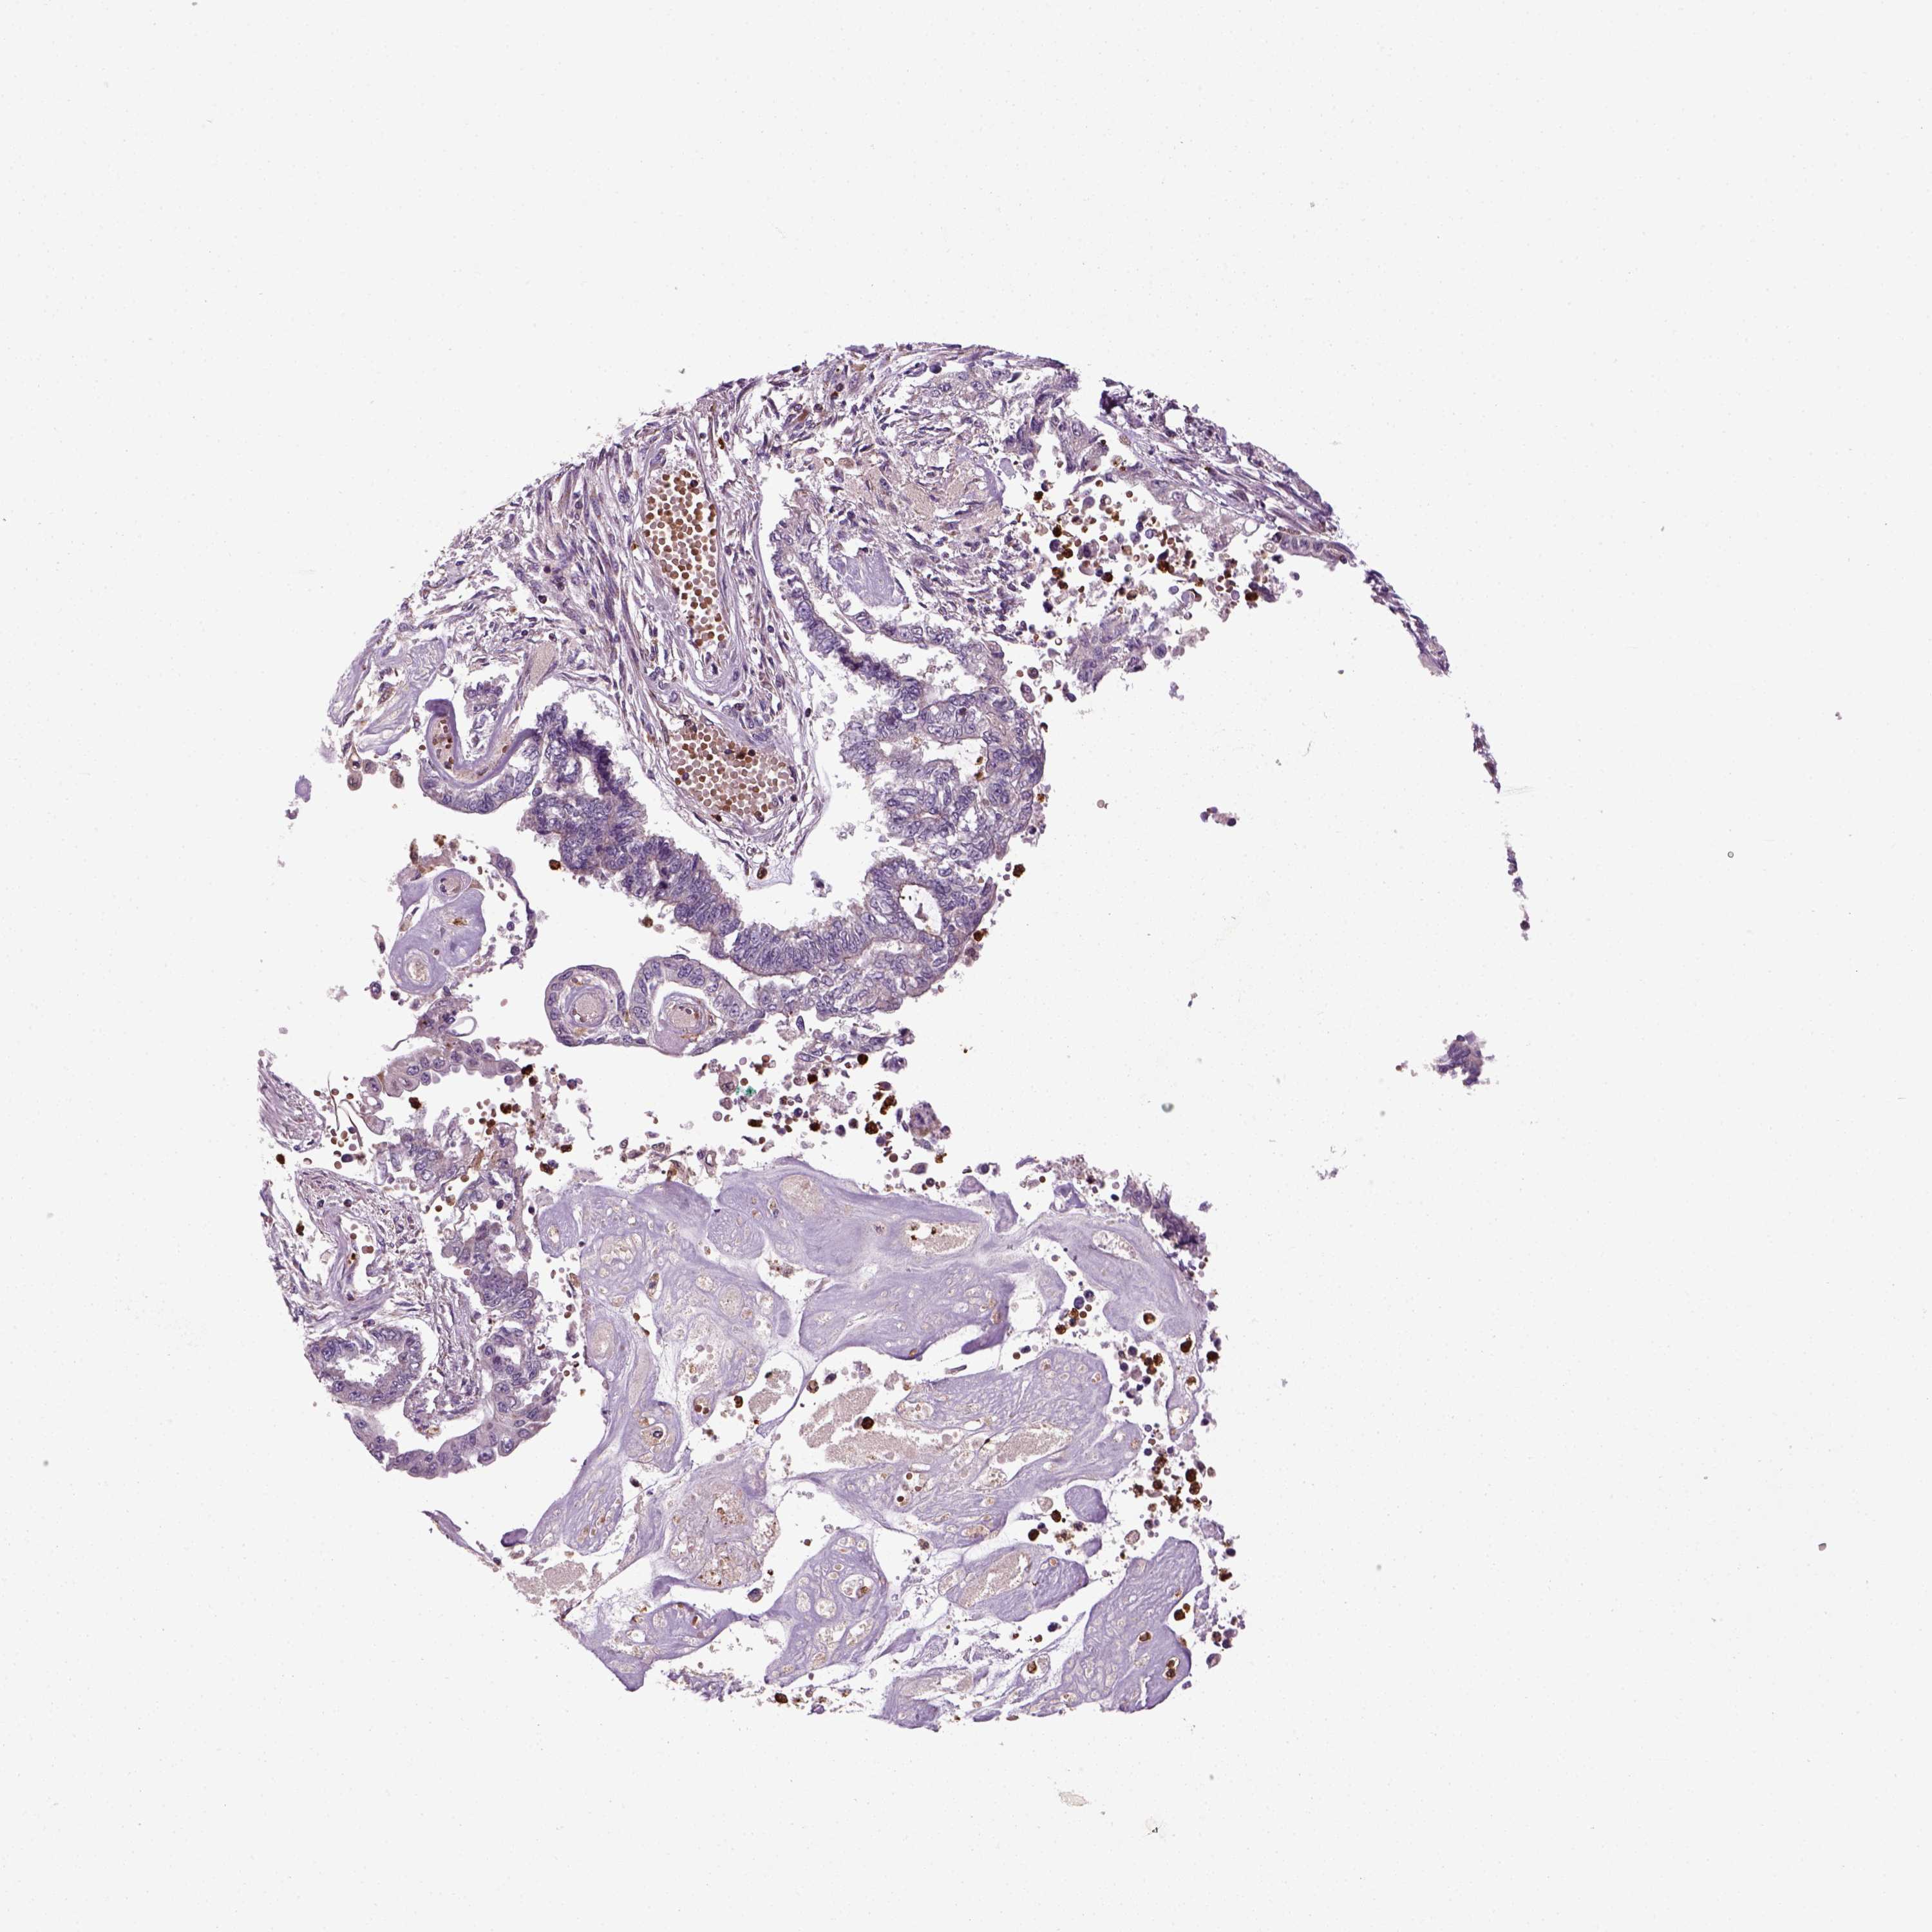

ENDOMETRIAL CANCER - Protein expressioni

A mouse-over function shows sample information and annotation data. Click on an image to view it in a full screen mode. Samples can be filtered based on level of antibody staining by selecting one or several of the following categories: high, medium, low and not detected. The assay and annotation is described here.

Note that samples used for immunohistochemistry by the Human Protein Atlas do not correspond to samples in the TCGA dataset.

Antibody stainingi

Antibody staining in the annotated cell types in the current human tissue is reported as not detected, low, medium, or high, based on conventional immunohistochemistry profiling in selected tissues. This score is based on the combination of the staining intensity and fraction of stained cells.

Each image is clickable and will lead to virtual microscopy that enables deeper exploration of all samples and also displays staining intensity scores, fraction scores and subcellular localization as well as patient and tissue information for each sample.

Antibody HPA044186

Antibody HPA063605

Staining

High

Medium

Low

Not detected

Intensity

Strong

Moderate

Weak

Negative

Quantity

>75%

75%-25%

<25%

None

Location

Nuclear

Cytoplasmic/membranous

Cytoplasmic/membranous,nuclear

Adenocarcinoma, NOS

Adenocarcinoma, metastatic, NOS